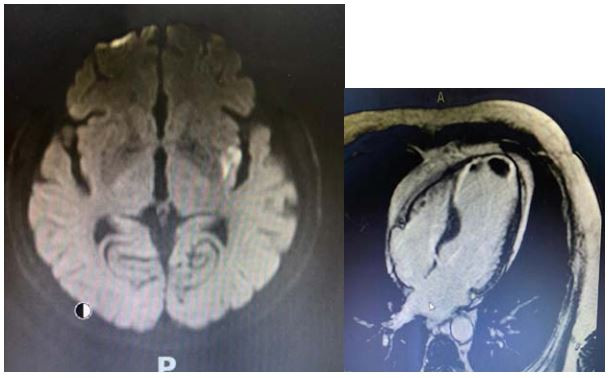

Homem de 56 anos hipertenso bem controlado com diagnóstico prévio de doença arterial coronária (IAM há 4 anos) em uso de AAS 100mg/dia, metroprolol 50mg/dia, atorvastatina 20mg/dia e valsartana 360mg/dia é admitido com quadro súbito de afasia. Foi submetido a trombólise com melhora completa dos sintomas. ECG mostrava ritmo sinusal e área inativa anterior. Na investigação realizou Holter-24hs que mostrou ritmo sinusal com raras extra sístoles atriais. Doppler de carótidas sem aterosclerose significativa. Realizou ressonância magnética do crânio e do coração com imagens representadas a seguir:

Qual alternativa melhor descreve a origem da afasia do paciente: